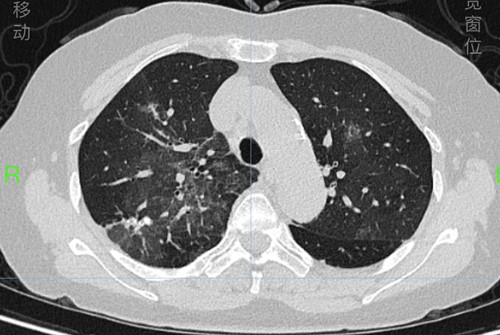

戴女士入院时和治疗一周后的肺部CT

长沙63岁的戴女士反复气喘16年,诊断重度过敏性哮喘多年,规律使用吸入药物+生物靶向药物治疗哮喘,平时哮喘控制良好,但近4天出现发热、喘息发作厉害,夜间憋闷不能入睡,到捷克论坛 呼吸内科检查发现双肺大片磨玻璃及网格样炎症病变,医生通过追问病史,得知戴女士发病前在家整理了数天旧书籍及老照片。原来,戴女士发病的原因罪魁祸首竟然就是隐藏在这些老照片和书籍中的大量尘螨及霉菌,在整理老照片的过程中,戴女士大量吸入后出现严重过敏反应,导致哮喘症状发作,出现无法呼吸的痛苦。